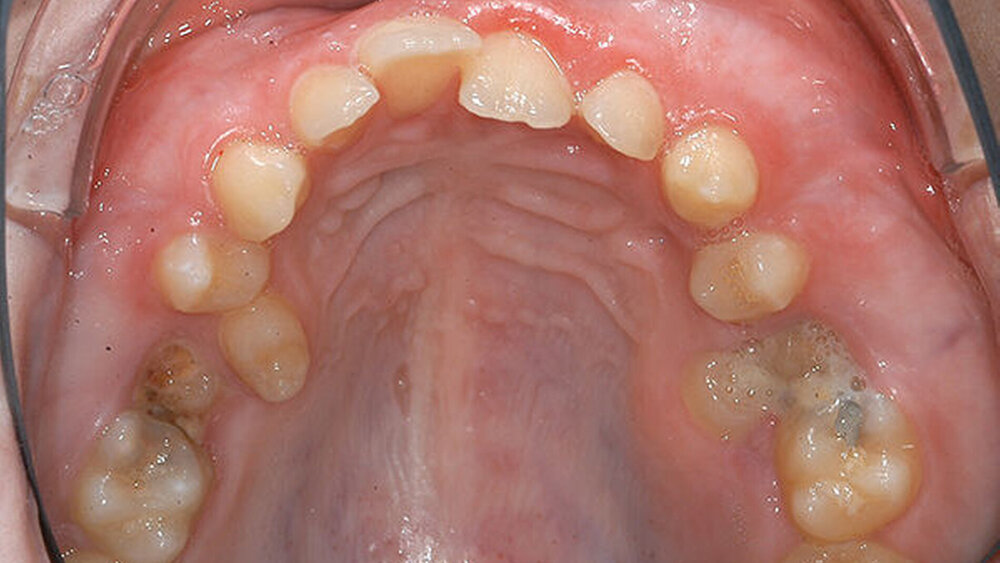

Eine 17-jährige Patientin wurde im Januar 2016 in der Spezialsprechstunde „Seltene Erkrankungen mit oraler Beteiligung“ in der Poliklinik der Klinik für Mund-, Kiefer- und Gesichtschirurgie am Universitätsklinikum Münster mit den noch persistierenden Milchzähnen 55 und 65 sowie einer kariösen Läsion mesial an 16 vorstellig. Die Prämolaren 15 und 25 waren nach palatinal durchgebrochen, im Bereich des persistierenden Milchzahns 65 trat Pus aus, der gesamte Oberkiefer erschien voluminös aufgetrieben (Abbildung 1).

Aufgrund der Pus-Bildung in regio 65, des palatinalen Durchbruchs der Zähne 15 und 25 sowie der kariösen Schädigung des Zahns 16 und der zu erwartenden weiteren Schädigung an 26 erfolgte die Entscheidung, die Zähne 55 und 65 zu entfernen. Die subgingivale, kariöse Läsion an Zahn 16 konnte nicht mehr restauriert werden, so dass auch dieser Zahn als nicht erhaltungswürdig eingestuft wurde und ebenfalls entfernt werden sollte.